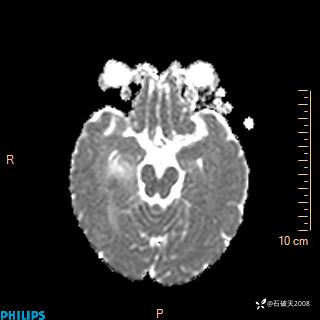

ADC